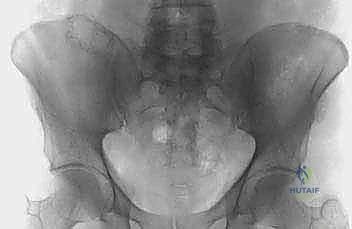

- التصوير بالأشعة السينية (X-rays): الفحص المبدئي لرصد أي تآكل أو تدمير في البنية العظمية للحوض ومفصل الورك.

- التصوير المقطعي المحوسب (CT Scan): يقدم صوراً ثلاثية الأبعاد تُظهر بدقة متناهية مدى تدمير القشرة العظمية، وهو الفحص الأهم للتخطيط الجراحي وتحديد خطر حدوث الكسور المرضية.